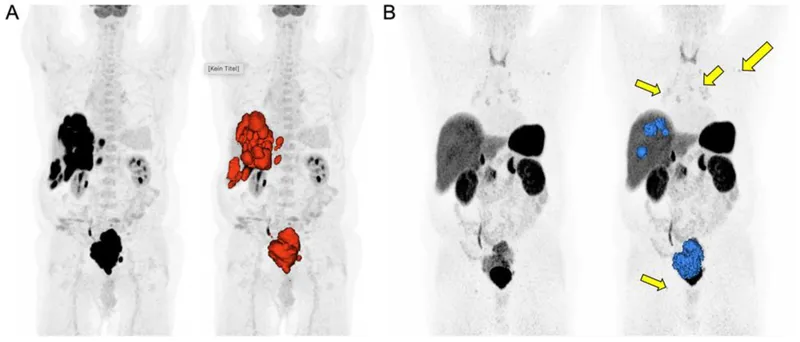

- ⁶⁸Ga-DOTATATE PET/CT: Gold standard for SSTR imaging.

⭐ ⁶⁸Ga-DOTATATE PET/CT offers superior sensitivity over Octreoscan for detecting SSTR-positive NETs and is crucial for staging and PRRT planning.